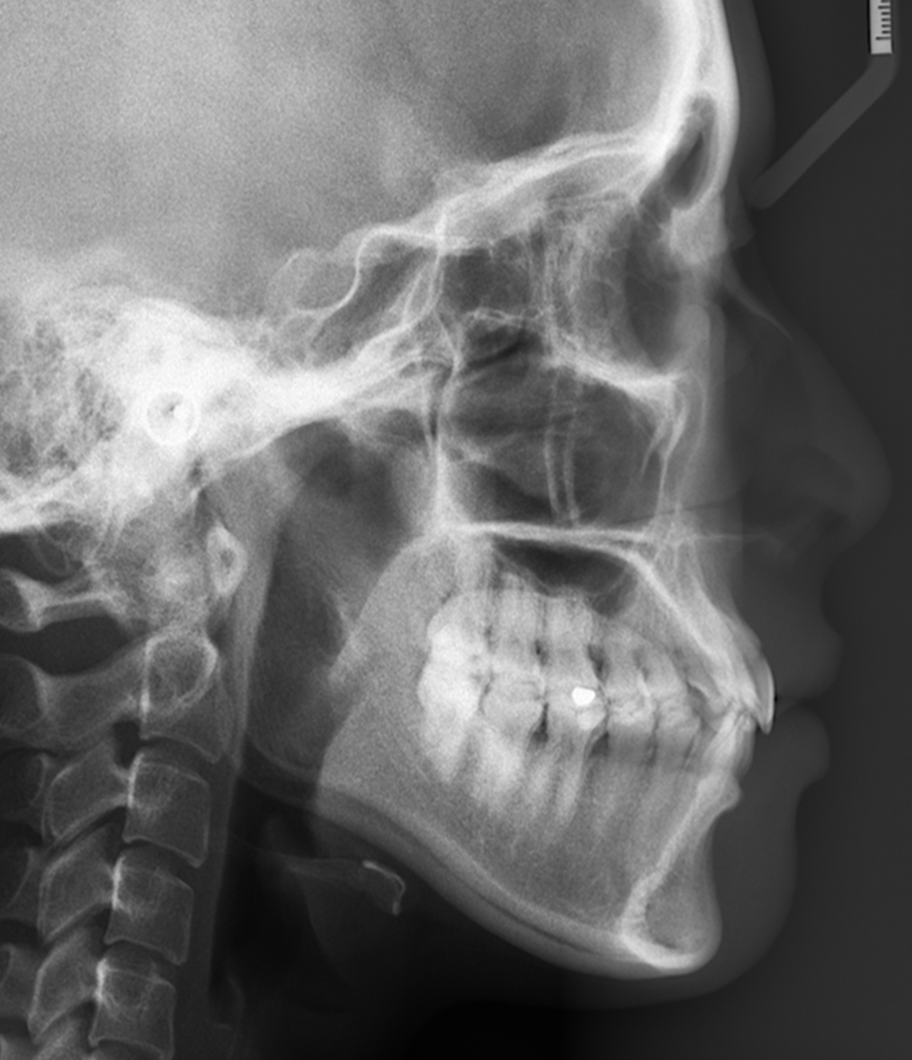

再好的医生也通过X光片,通过头影测量,协助判断:你骨性还是牙性?正畸是否能解决你的问题?你牙齿“错”在哪里?"错"了多少?以及预测牙齿矫正后的变化。

正畸医生要综合无数指标来判断骨性牙性,放出了其中一小个供参考的角度。通过头颅侧位片来观察颅骨、颌骨的长、宽、高发育情况,并进行许多测量分析即"透过现象看本质","深入内部"的检查,依次做出的诊断才更全面、更可靠,此后医生的治疗才会胸有成竹。

所以,头影测量不是一句两句能讲清楚的,更不是你网上查查就能知道的!分析你是骨性还是牙性问题,要靠专业医生的测量判断!你只要记住,眼睛看到的都是虚的,只有数字分析的结果才可靠!乖乖听医生话!

拍X光牙齿及头部骨头照片。目的是为了看你的牙齿及骨骼发展方向等,以利于以后制定准确的矫正方法。